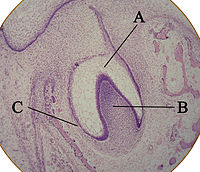

The tooth bud (sometimes called the tooth germ) is an aggregation of cells that eventually forms a tooth. These cells are derived from the ectoderm of the first branchial arch and the ectomesenchyme of the neural crest. The tooth bud is organized into three parts: the enamel organ, the dental papilla and the dental follicle.

The enamel organ is composed of the outer enamel epithelium, inner enamel epithelium, stellate reticulum and stratum intermedium. These cells give rise to ameloblasts, which produce enamel and the reduced enamel epithelium. The location where the outer enamel epithelium and inner enamel epithelium join is called the cervical loop. The growth of cervical loop cells into the deeper tissues forms Hertwig's Epithelial Root Sheath, which determines the root shape of the tooth.

The dental papilla contains cells that develop into odontoblasts, which are dentin-forming cells. Additionally, the junction between the dental papilla and inner enamel epithelium determines the crown shape of a tooth. Mesenchymal cells within the dental papilla are responsible for formation of tooth pulp.

The dental follicle gives rise to three important entities: cementoblasts, osteoblasts, and fibroblasts. Cementoblasts form the cementum of a tooth. Osteoblasts give rise to the alveolar bone around the roots of teeth. Fibroblasts develop the periodontal ligaments which connect teeth to the alveolar bone through cementum.

The first signs of an arrangement of cells in the tooth bud occur in the cap stage. A small group of ectomesenchymal cells stops producing extracellular substances, which results in an aggregation of these cells called the dental papilla. At this point, the tooth bud grows around the ectomesenchymal aggregation, taking on the appearance of a cap, and becomes the enamel (or dental) organ. A condensation of ectomesenchymal cells called the dental follicle surrounds the enamel organ and limits the dental papilla. Eventually, the enamel organ will produce enamel, the dental papilla will produce dentin and pulp, and the dental follicle will produce all the supporting structures of a tooth.

The bell stage is known for the histodifferentiation and morphodifferentiation that takes place. The dental organ is bell-shaped during this stage, and the majority of its cells are called stellate reticulum because of their star-shaped appearance. Cells on the periphery of the enamel organ separate into three important layers. Cuboidal cells on the periphery of the dental organ are known as outer enamel epithelium. The columnar cells of the enamel organ adjacent to the dental papilla are known as inner enamel epithelium. The cells between the inner enamel epithelium and the stellate reticulum form a layer known as the stratum intermedium. The rim of the dental organ where the outer and inner enamel epithelium join is called the cervical loop. In summary, the layers in order of innermost to outermost consist of dentine, enamel (formed by inner enamel epithelium, or 'ameloblasts', as they move outwards/upwards), inner enamel epithelium and stratum intermedium (specialised stratified cells that support the synthetic activity of the Inner Enamel Epithelium) What follows is part of the initial 'enamel organ', the middle of which is made up of stellate reticulum cells. This is all encased by the outer enamel epithelium layer.